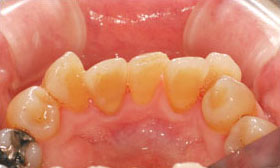

主な目的は、虫歯・歯周病の原因となるプラーク(ネバネバしたお口の中の細菌のかたまり)を効果的に除去することですが、副次的効果として、歯の黄ばみ等も一緒に除去できるため、本来の歯の色合いを回復させることができます。

クリーニングで歯の汚れを除去した症例。リスクは、特にない。